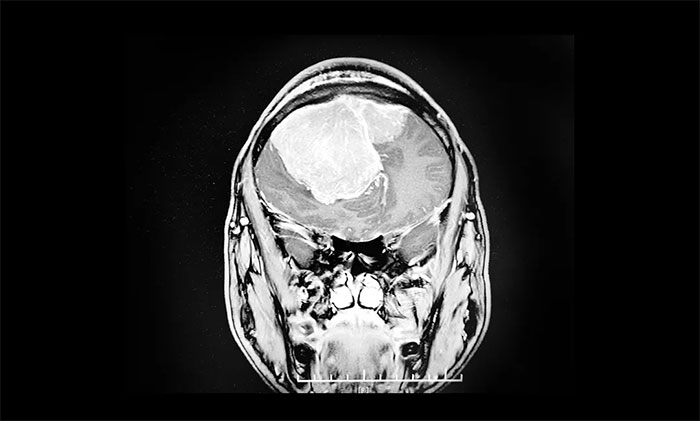

蓝十字为张先生制定了详尽的检查计划,其中头颅MRI提示,双侧额部见一团块状异常信号病灶,肿块跨中线生长,周围可见大片状水肿信号,双侧侧脑室受压明显、移位变形,中线结构左侧偏移。临近额骨骨质破坏。

潘仁龙主任、顾国山教授、吴治群博士经过多次会诊讨论最终得出:患者脑部肿瘤是双侧矢状窦旁脑膜瘤,11cm的瘤体已覆盖整个额部。且患者脑疝形成,手术指征明确,需立即进行手术,切除瘤体。

▲ 双侧矢状窦旁脑膜瘤,跨中线生长